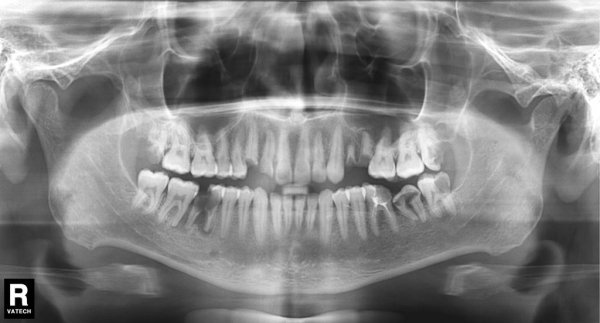

Здравствуйте! Хотелось бы получить общую консультацию по снимку. Очень плохие зубы с детства, постоянно беспокоят и просто разрушаются. Хотелось бы понять — есть возможность спасти хотя бы корни большинства зубов? Существуют ли вообще очень серьезные проблемы?

Добрый день. Особых проблем я не вижу, уважаемый пациент. 4.7 зуб необходимо тщательно осмотреть на предмет пригодных тканей для последующего восстановления вкладкой и коронкой, на 4.6 также есть воспаление на верхушке корня, все также необходимо пролечить затем изготовить культевую вкладку и коронку, 3.6 необходимо перелечить, плохая некачественная пломбировка, а также большая по площади пломба, при неблагоприятном исходе может привести к сколу стенки, что в последствии также к потере зуба, 2.6 скорее всего удалится, но еще раз стоит сделать ревизию, 1.6 необходимо перелечить.